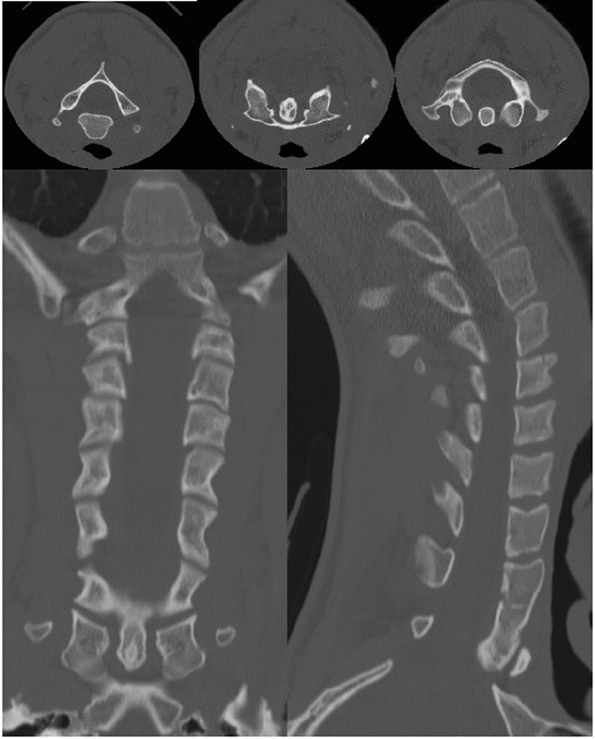

MRI is superior in demonstrating spinal cord pathology and

osseous injury. However, injuries purely localized to the transverse

these types of injuries, direct coronal CT can provide superior demonstration of skeletal features in the upper cervical spine.212

![]() |

FIGURE 41-8 Images from a screening cervical spine CT.